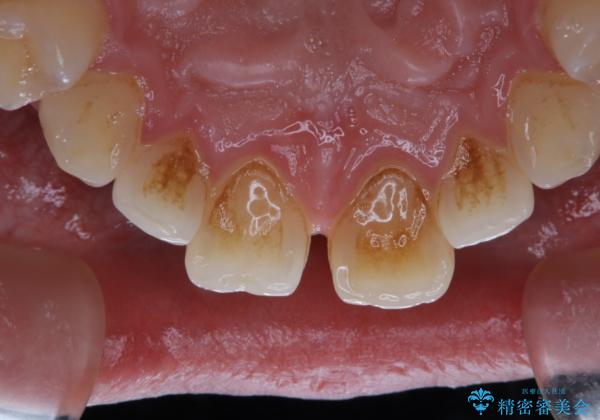

- 矯正治療を考えていて、歯科医院が久しぶりのためまずはクリーニングしたいとのことでした。PMTC60分コースを行いました。

矯正治療中は虫歯や歯周病リスクが高くなることがあります。

インビザライン矯正治療はマウスピースで1日20時間以上歯列全体を覆っているため、歯石や汚れなどが付着したままだと、フィットが悪くなったり、口臭が強く出たりする原因につながることもあります。

今後、矯正を考えている場合は、まず現状の口腔内をチェックし、虫歯や歯周病などを早期に発見し進行を防ぐことが大切です。